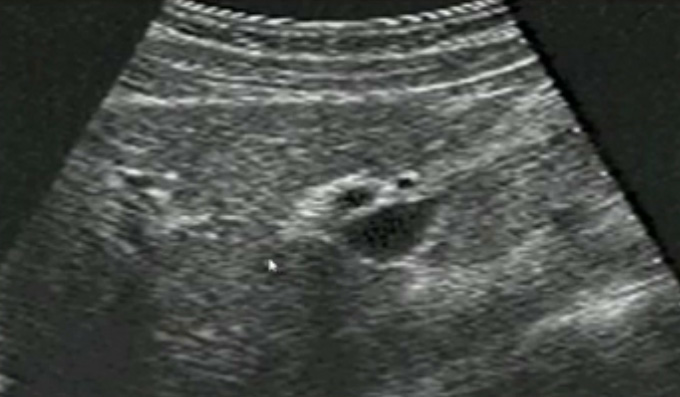

一、正常膽囊超聲圖像有的時(shí)候經(jīng)常發(fā)現(xiàn)檢查不到膽囊,其實(shí)有幾種可能性,檢查人員的技術(shù)不過關(guān)沒發(fā)現(xiàn)膽囊,就要找上級醫(yī)生會診,如果還是沒找到的話就不是技術(shù)問題。結(jié)石或腫瘤充滿膽囊,使其液腔消失,慢性膽囊炎使得膽囊萎縮或膽囊壁肥厚而囊腔消失患者已進(jìn)食,膽囊處于膽汁排空的狀態(tài),膽囊先天性過小或缺失;膽囊位置極端異常(可能很低或位于左側(cè))膽囊切除術(shù)后(注意詢問病史)。